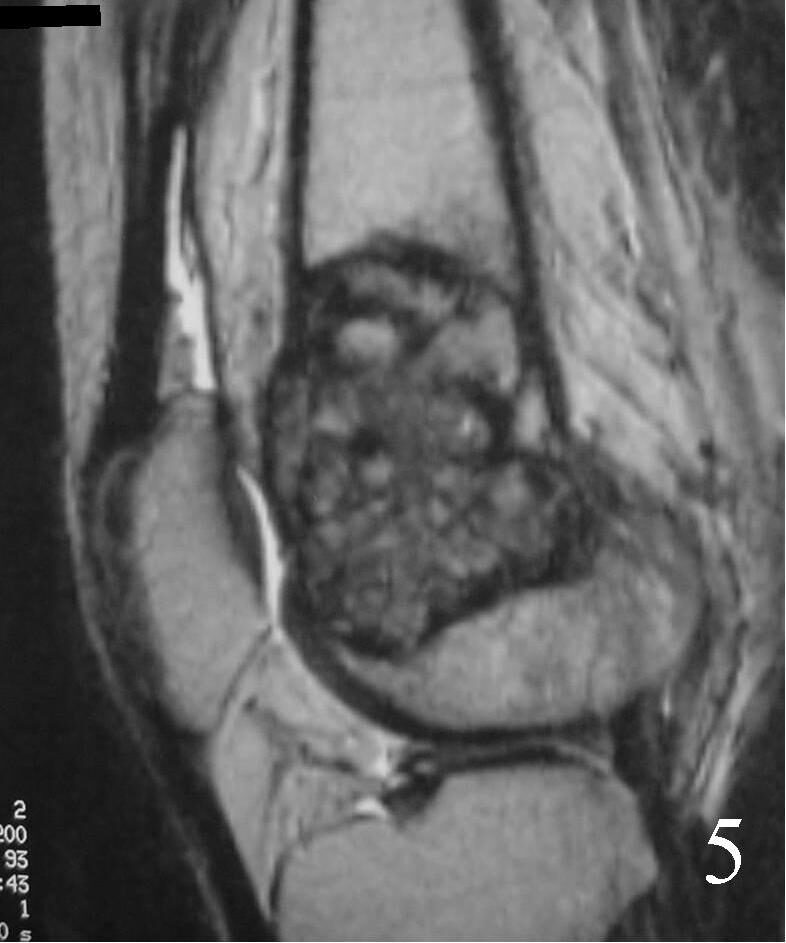

MRI

- They will be low to intermediate on T1-weighted images, and intermediate to high on T2-weighted images (Fig. 4, 5, 6)

Fig. 5 Sagittal T1 MRI shows the soft tissue extension anteriorly.

Fig. 6 Sagittal T2 FS MRI shows high and low signal areas (heterogeneous)